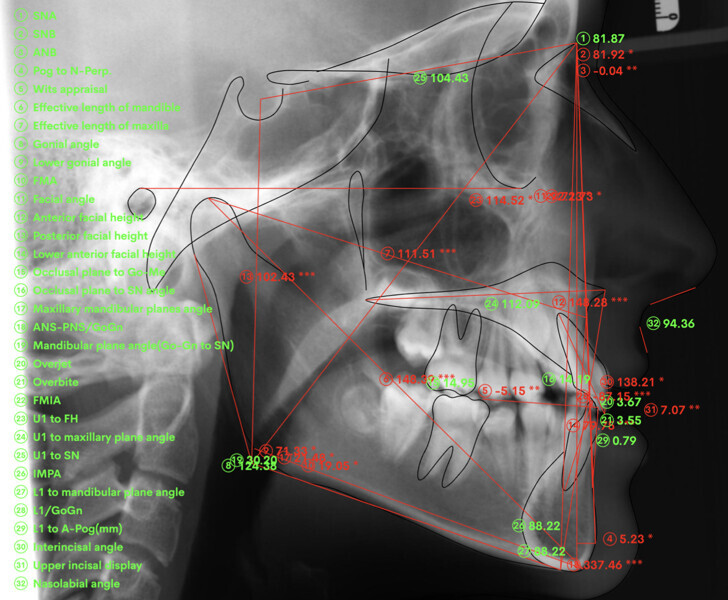

A 14-year-old female patient presented with the chief complaint of midline deviation and dental crowding in both arches. Facial analysis showed a hypodivergent growth pattern, a normal nasolabial angle, a harmonious profile and proper chin projection. Clinical examination revealed a Class III skeletal relationship (ANB = 0°) and Class I molar relationship. The maxillary right canine was absent, and this had led to space loss and mesial drift of posterior teeth on the right side, resulting in a slight Class II molar relationship. The maxillary left canine had erupted in a high position. The mandibular arch displayed crowding despite the agenesis of the right second premolar and the persistence of the primary molar (Figs. 3–11). The radiograph showed the probably premature loss of the maxillary right primary canine and consequently impacted maxillary right permanent canine, and the agenesis of the mandibular right second premolar and the mandibular right third molar (Fig. 12).

Cephalometric analysis showed normal incisor inclination (U1–PP = 112°) and slightly uprighted mandibular incisors (IMPA = 88°), consistent with dental compensation commonly observed in Class III skeletal malocclusions. Cephalometric analysis confirmed a reduced lower anterior facial height associated with a hypodivergent pattern (Figs. 13 & 14).